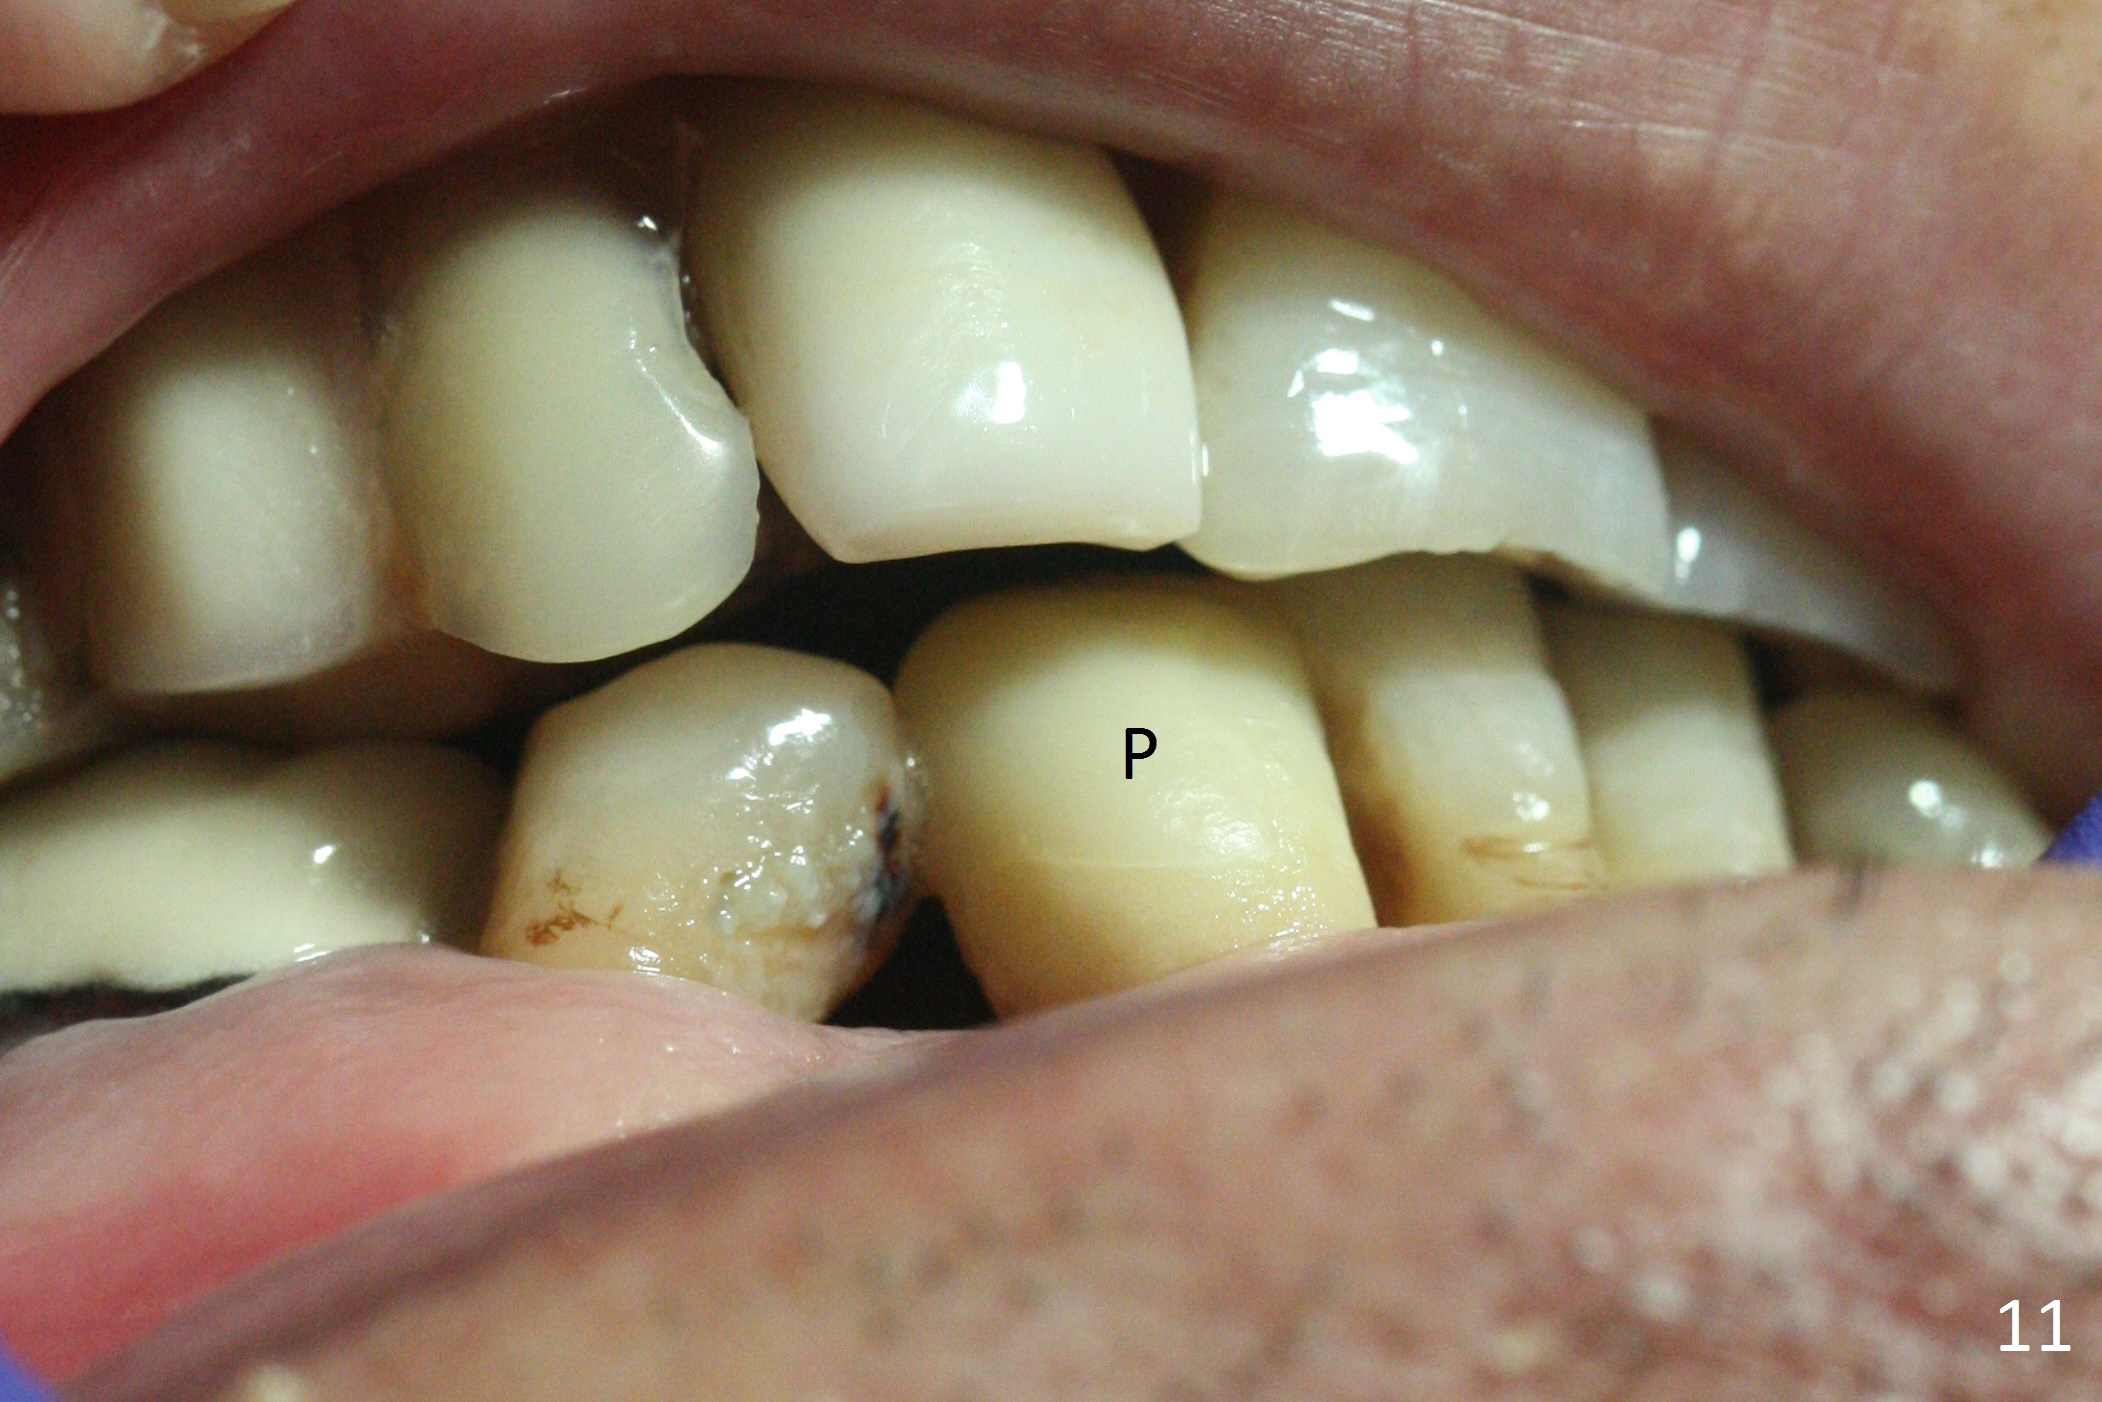

The lower dentition is special, consisting of a residual root (Fig.1 ^), 2 incisor (I), 1 canine (C), 1 premolar (P) and 1 molar (M). The residual root looks like an incisor with rotation of 90º (Fig.2,3). Osteotomy is initiated (Fig.4) for a 3x16(2) mm 1-piece implant (Fig.5 with 45 Ncm). The implant is being placed as distal as possible (Fig.4 arrow) so that a large canine-like provisional is to be fabricated in the large edentulous space (Fig.8,9) after bone graft (Fig.6,7 *). The gingiva around the provisional (Fig.10 P) remains healthy 11 days postop with occlusal clearance against the opposing dentition (Fig.11). The implant threads are not exposed with the help of bone graft 3 months 1 week postop (Fig.12). The gingiva around the implant is healthy (Fig.13). Soft tissue socket is formed by the provisional (Fig.14 *).